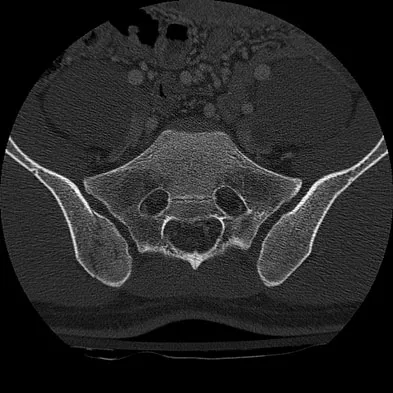

A 23-year-old man is involved in a motor vehicle accident. An AP radiograph is shown in Figure 29a, and axial and sagittal CT scans are shown in Figures 29b and 29c. Neurologic examination shows 1/5 strength of his quadriceps and iliopsoas on the right, with 1/5 quadriceps function on the left. Definitive treatment of his injury should consist of